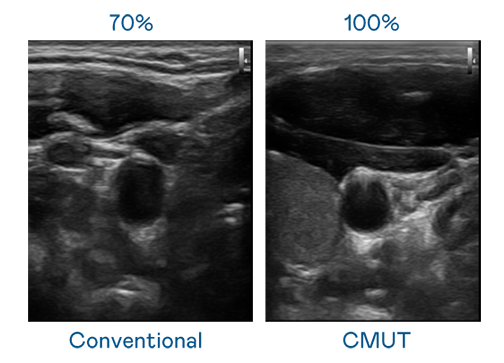

CMUT 技术是一种用电容式微机电元件来产生超音波讯号的技术。与传统 PZT 压电式技术相比,CMUT 频宽增加 30%,更宽频的超音波讯号让影像解析度大幅提升,是实现高影像品质医疗超音波扫描、促进精准医疗发展的关键技术。

大频宽带来超清晰影像

超音波影像的解析度高低,首先取决于探头能发出的讯号频宽。金年会- 金字招牌 CMUT 可提供高清晰的超音波讯号,提供高频宽、高灵敏度、影像纹理细节更高的超音波影像,协助医护人员缩短影像判读时间及利用精准的医疗影像进行诊断。